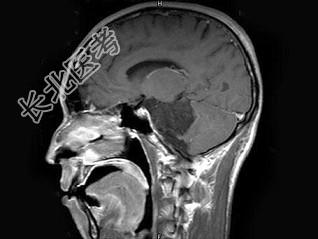

- 单项选择题男,38岁, 头痛半年余,MRI检查如图, 最可能的诊断是 ( )

A、听神经瘤

B、三叉神经瘤

C、表皮样囊肿

D、皮样囊肿

E、未见异常